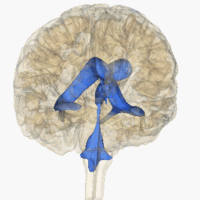

Rotating 3D rendering of the four ventricles and connections. From top to bottom:

Blue - Lateral ventricles

Cyan - Interventricular foramina (Monro)

Yellow - Third ventricle

Red - Cerebral aqueduct (Sylvius)

Purple - fourth ventricle

Green - continuous with the central canal

(Apertures to subarachnoid space are not visible)